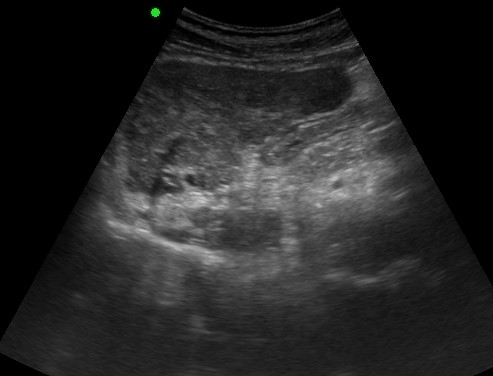

LIVER ) META |

2019.05.11 мЎ°нҡҢмҲҳ: 199 |